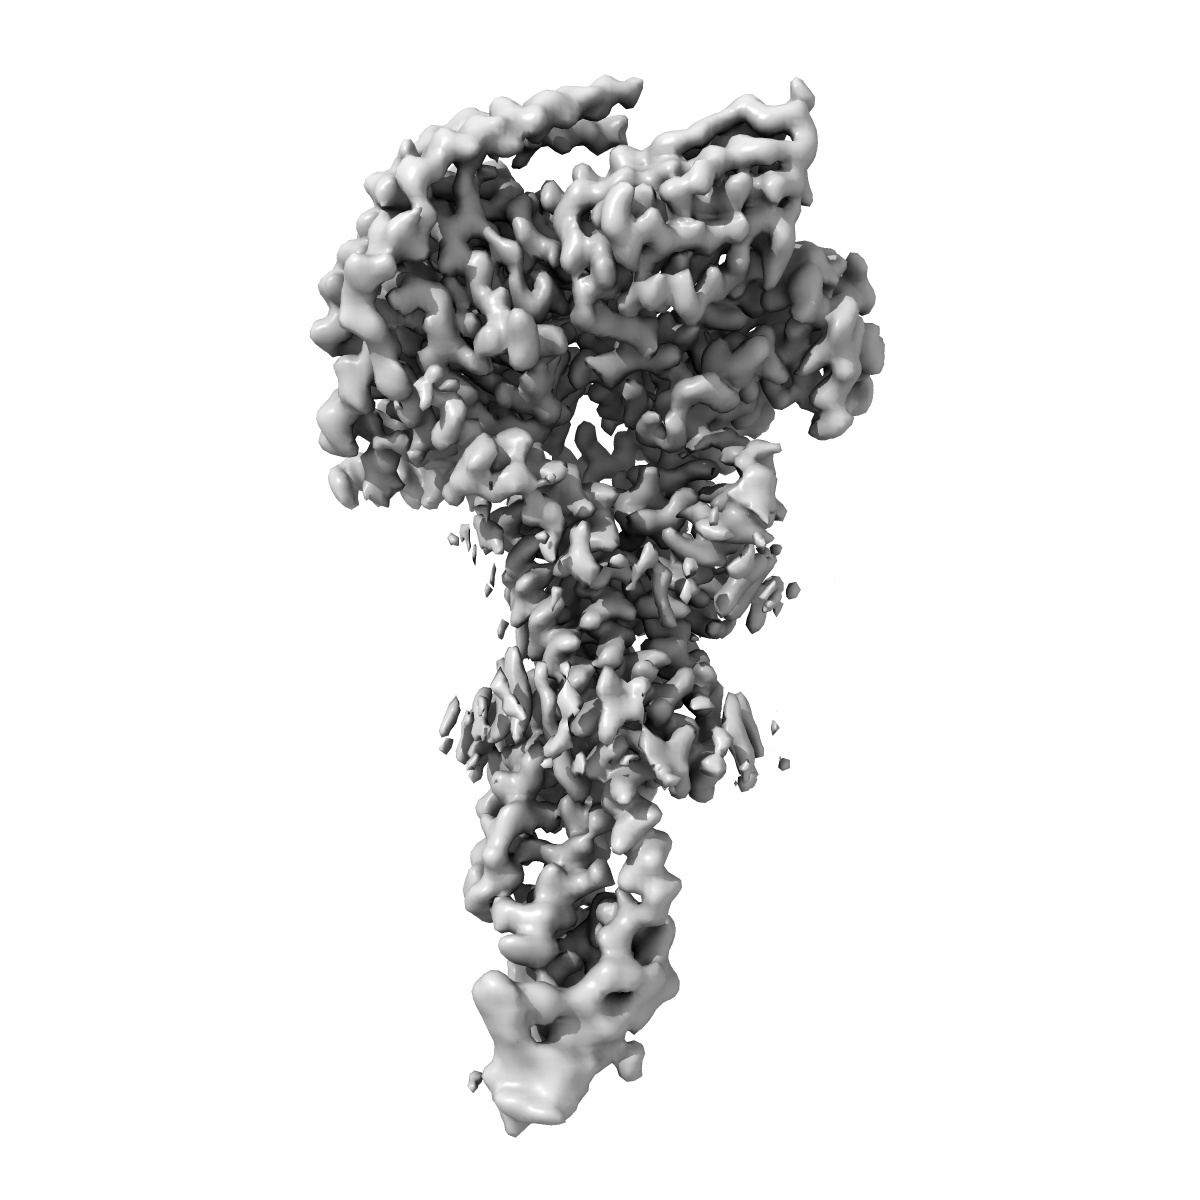

Cryo-EM structure of the GLP-1R/GCGR dual agonist MEDI0382-bound human GCGR-Gs complex

Single-particle2.91 Å

Sample: Cryo-EM structure of the GLP-1R/GCGR dual agonist MEDI0382-bound human GCGR-Gs complex

Structural analysis of the dual agonism at GLP-1R and GCGR.

(2023) PNAS , 120 , e2303696120 - e2303696120